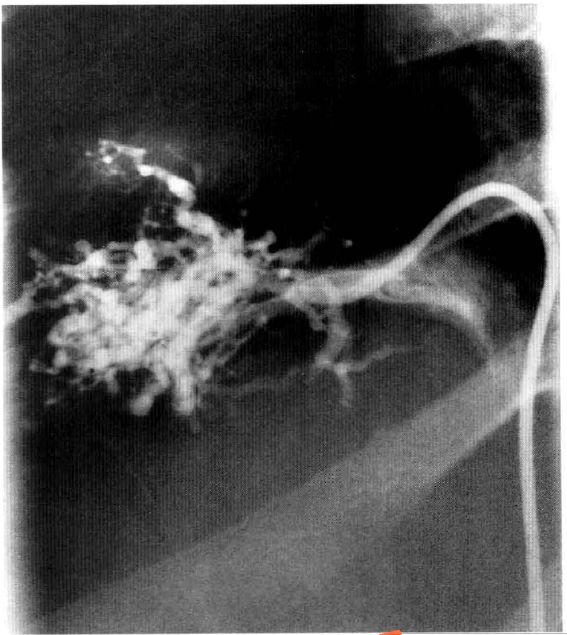

2.4 静脉造影

静脉造影是诊断该病的「金标准」。其典型表现为静脉狭窄、不规则,可在肝静脉汇入下腔静脉处或静脉入口远端发现血栓。代偿性的肝静脉表现为典型的「蜘蛛样」改变,也可见肝内侧支和再通静脉[3][4]。

图2 BCS患者的肝静脉造影,注意「蜘蛛样」表现(来源:见参考文献[6])